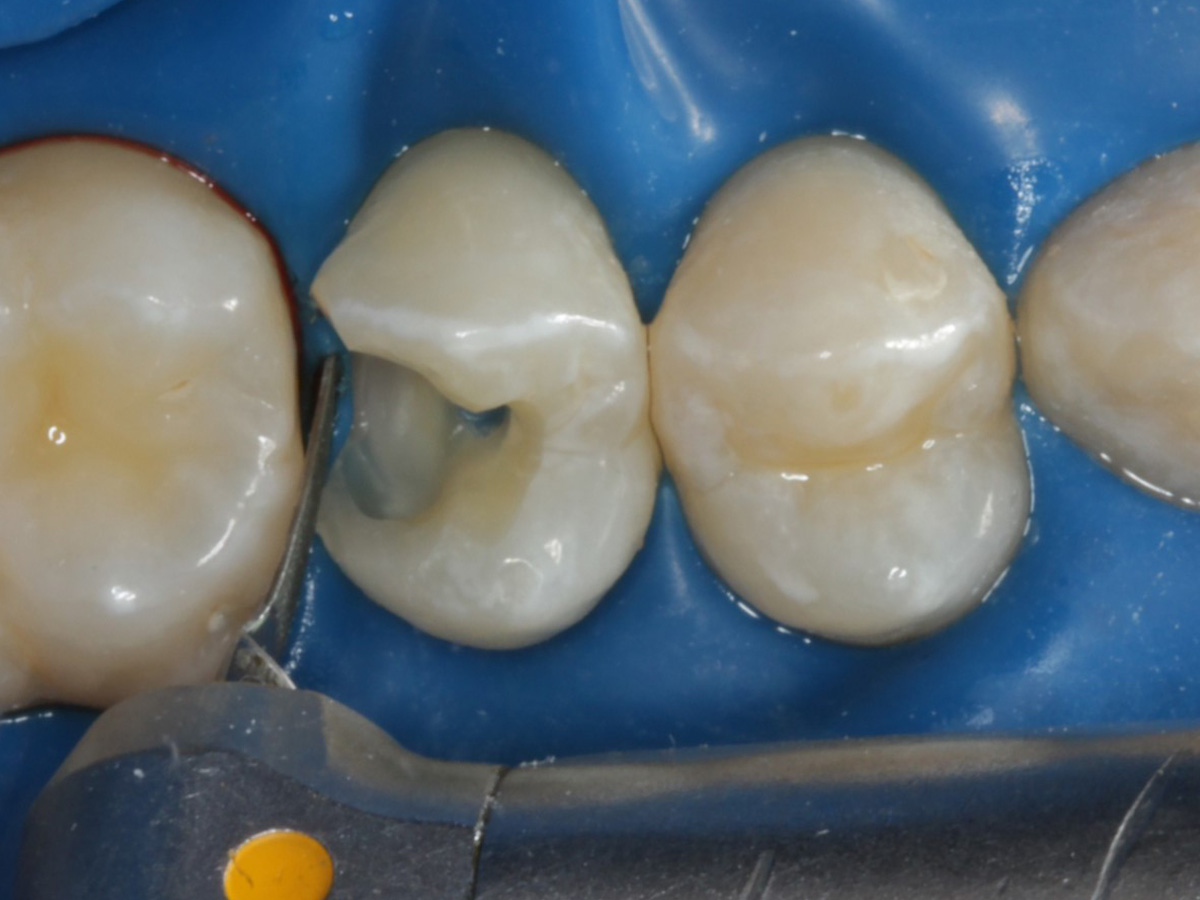

Matrize und Twinring entfernt;  weitere Lichthärtung von bukkal und oral

Abbildung 23

Abbildung 24

Folgesitzung: Trepanation Zahn 25